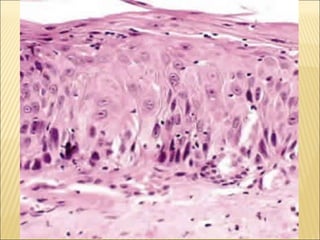

El documento describe la derivación y funciones del tejido epitelial. El tejido epitelial deriva del ectodermo, mesodermo intraembrionario y endodermo intraembrionario. Sus funciones principales son el sostén, protección, absorción, reabsorción, captar estímulos y secreción.